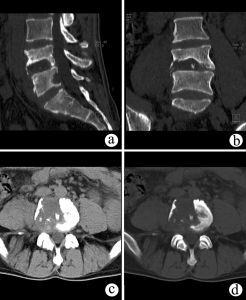

CT檢查可以清晰地顯示病灶部位,有無空洞和死骨形成。即使是小型的椎旁膿腫,在CT上檢查時也可發現。CT檢查對腰大肌膿腫有獨特的價值。